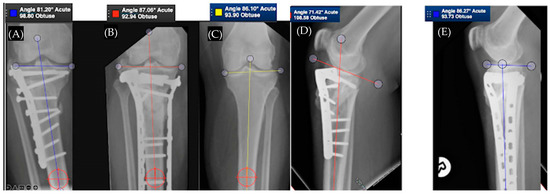

Figur 2 visar ett fall av proximal tibiafelunion behandlad med osteotomi och dubbelplattning. Figur 3 visar ett fall av proximal tibiamalunion behandlad med intraartikulär osteotomi.

Fall av en 54-årig kvinna med intraartikulär (går in i leden)malunion av proximala tibia med 5 mm lateral depression och 13 graders varusdeformitet (första bildraden). CT-skanning visas i den andra bildraden. Patienten behandlades med en lateral parapatellär metod med en lateral tibial tuberkelosteotomi och en falluckosteotomi. De deprimerade fragmenten lyftes följt av en öppningskils tibialosteotomi. Mediala och laterala plattor applicerades för att hålla repositionen (tredje bildraden).

En posterior metod användes för att avlägsna fibrös vävnad och mobilisera det felaktigt förenade fragmentet. Ledkongruensen återställdes och fixationen säkrades med en posterior stödplatta och dragskruvar.

Marti och Kerkhoffs [8,9] utförde snedställda osteotomier på 23 patienter med lateralt tibialplatådepression och valgusmalunion av proximala tibia. Deras indikationer för operation inkluderade: en valgusfelställning på stående AP-röntgen (8 till 20 grader); och depression av det laterala tibialplatået på 3–21 mm.

Författarna använde en lateral metod och en lateral tibial sned osteotomi. Exponeringen sker via ett lateralt parapatellärt tillvägagångssätt med osteotomi av Gerdes tuberkel för att visualisera de främre 60 % av platån, och om en mer posterolateral vy krävs kan osteotomi av fibulahuvudet också utföras. De beskrev en varus-skapande öppningskil-osteotomi av den laterala tibia-platån ovanför tibialtuberkeln baserad på ett medialt gångjärn, vilket kan vara biplanärt. Det nedtryckta tibia-platåsegmentet osteotomiseras genom det extraartikulära fönstret av öppningskil från nedifrån, och höjs med en tamp för att återskapa ledytan. Efter korrigering av patientens alignment fylls osteotomin med benmärgstransplantat och det nedtryckta segmentet med kortikokancellösa kilar som stöds med en lateral stötplatta [7,8].

De uppnådde en förbättring av det genomsnittliga tibiofemorala vinkeln från 13 till 4,4 grader, en förbättring av den genomsnittliga laterala sänkningen från 7,7 mm till 1,7 mm. Enligt Insall et al.s poängsystem [9] hade 20 av patienterna ett utmärkt eller gott resultat [8].

Yang et al. använde CT-genererade 3D-printade modeller för att planera osteotomiska snitt för sju patienter som led av posterolaterala tibialplatåmalunioner. Patienterna hade nedsänkta fragment mellan 4 och 12 mm, med ett genomsnitt på 9,4 mm. De använde den 3D-printade modellen för att bestämma längd och djup på sina osteotomiska snitt, vilka framgångsrikt reproducerades under operationen [10]. Deras tillvägagångssätt till den laterala tibialplatån liknade det som Marti och Kerkhoffs använde [8,9], men deras osteotomi var en öppna-dörr-osteotomi (gångjärn) av den laterala tibialplatån. De osteotomiserade sedan den nedsänkta segmentet bort från den laterala öppna dörren och höjde det med en stamp. Defekten fylldes med transplantat, den öppna dörren stängdes, och en lateral platta användes för att stötta osteotomin.

Vid 12-månadersuppföljningen hade alla sju patienter uppnått fraktur-läkning. Vid denna tidpunkt hade både Rasmussen anatomi- och funktionspoäng förbättrats för samtliga sju patienter (från 8,3 till 16,9 respektive från 15,9 till 26). Dessutom var platåkollapsen mindre än 1 mm hos alla sju patienter [11].

Mastrokalos et al. [11], Kfuri/Schatzker [12], Furnstahl et al. [13] och Van Nielen et al. [14] beskrev korrigeringar av nedsjunkna och valgus-laterala tibialplatåmalunioner genom ett lateralt tillvägagångssätt (var och en i enstaka fall), en ”open-book”-osteotomi av den laterala kortexen, liknande Yang et al. [11]. De kunde korrigera deformiteter på 10 till 20 graders valgus med en nedsjunkning på 3,6 till 15 mm till normal justering och korrigerade nedsjunkningen. Deras patienter återfick full rörlighet, var smärtfria och återgick till normal aktivitet. Furnstahl [13] använde datorassisterad planering med 3D-modellering och skärguider i sin rapport och korrigerade även en sagittal deformitet.